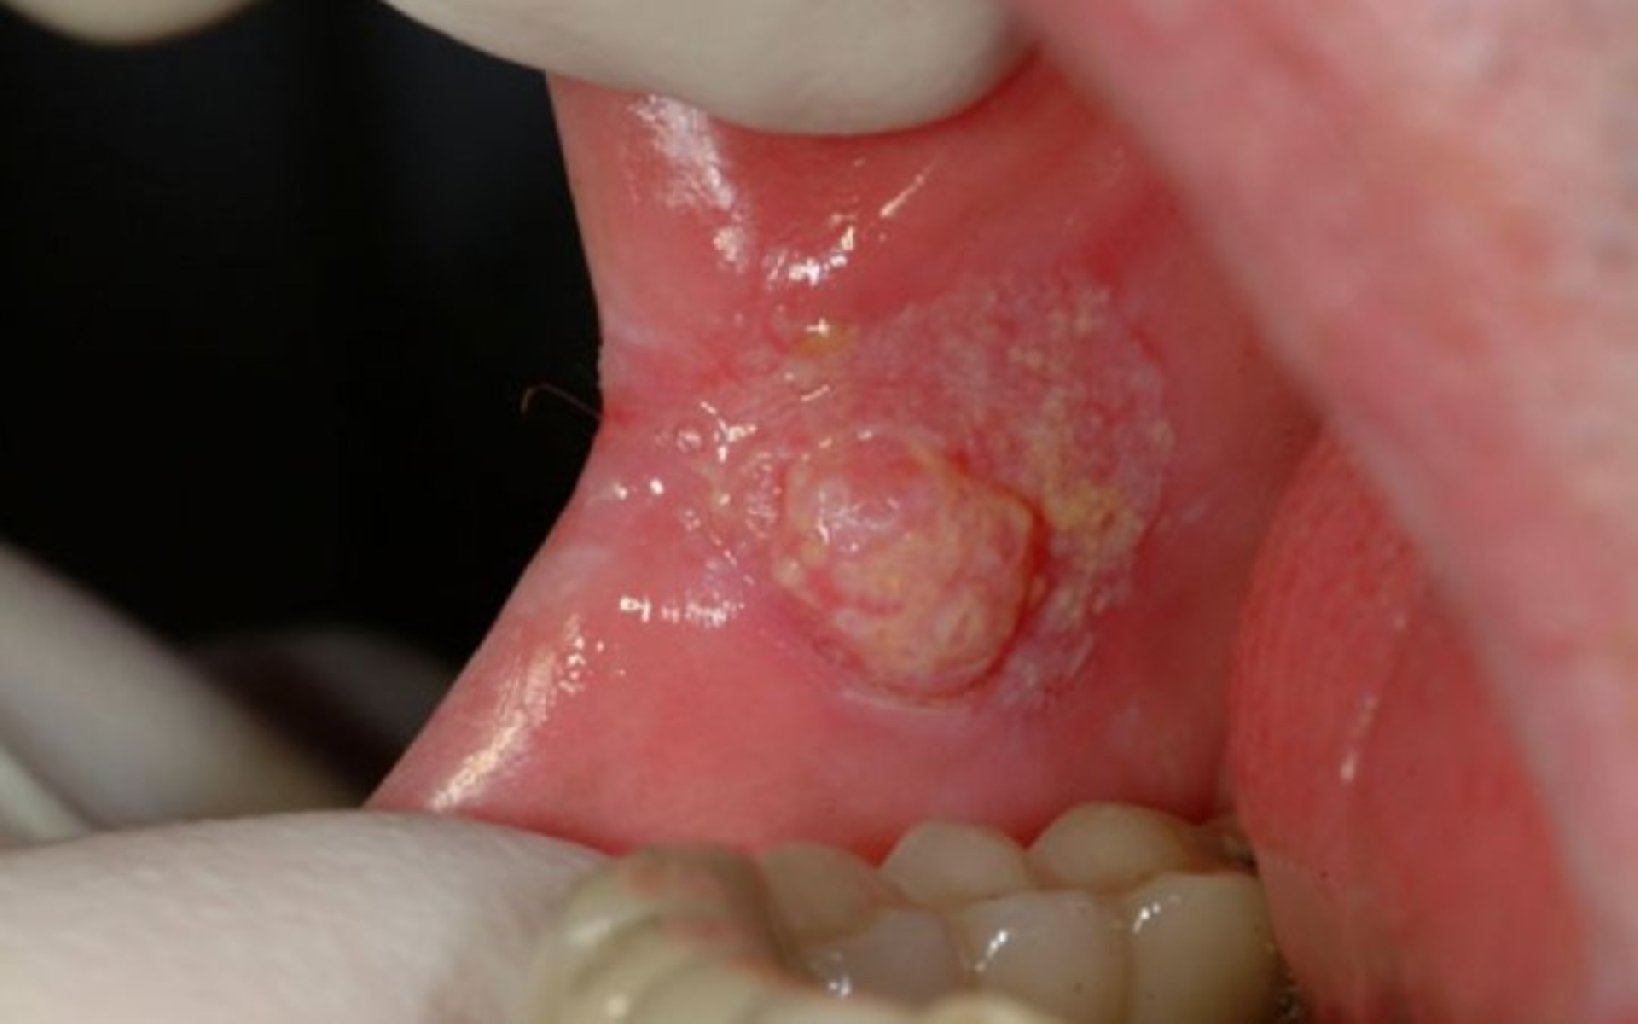

Aftöz Stomatit (Ağız Yaraları): Ağız boşluğunda təkrarlanan, ağrılı yaraları ifadə edir. Müalicə, si ...